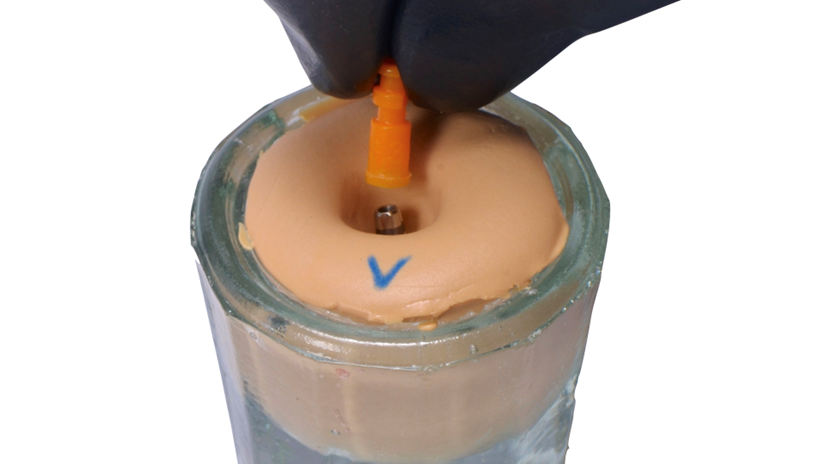

A paciente apresentava queixas estéticas e funcionais. Após avaliação clínica e radiográfica, optou-se pela substituição do pilar reto por um pilar Ideale angulado de 17 graus e 3,3 mm de diâmetro. Esse componente mais estreito e angulado permitiu corrigir o eixo emergente da futura coroa, viabilizando o planejamento de uma prótese parafusada na região estética.

O caso foi conduzido com planejamento cuidadoso, moldagens analógicas e provas clínicas. A reabilitação foi finalizada com a instalação de uma coroa metalocerâmica parafusada, garantindo estética, funcionalidade e reversibilidade do conjunto protético.